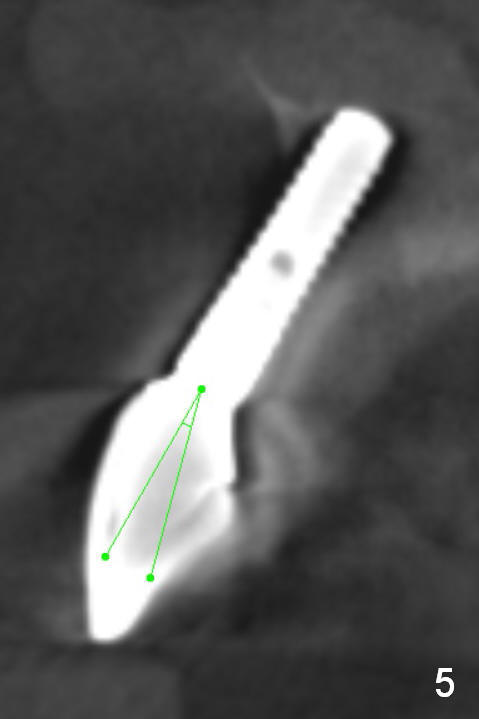

The implant at the site of #8, which was placed ~ 2 years ago, appears devoid of bone buccally (Fig.1 (CBCT 3 D image) I). Fig.2,3 are coronal sections of the tooth #9 (B: buccal) and 8 (A: Zirconium abutment), respectively. Fig.4 is a coronal section of the tooth #5 post-immediate implant with the bone plate (>, different case). With placement of a 15° Titanium abutment (Fig.5 palatal green line), the crown profile may improve.

It appears that there is not enough bone left for a new implant to be placed if the existing one is to be removed (Fig.3,5,15). What is the most likely to be seen at surgery?